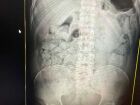

O homem, de 56 anos, deu entrada no Hospital Regional de Campo Grande no domingo (23), após ingerir álcool automotivo na cidade de Nova Alvorada do Sul. Assim, acabou morrendo na manhã desta segunda-feira (24).

Conforme o boletim de ocorrência, a vítima havia dado entrada no hospital com a consciência rebaixada, após passar vários dias ingerindo bebidas alcoólicas. Inclusive, teria consumido também álcool automotivo.

Entretanto, pela manhã, a vítima apresentou assistolia, ausência de atividade elétrica no coração sem retorno. Na sequência, apresentou PCR (parada cardiorrespiratória) e acabou falecendo.